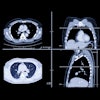

Pending the results of large, randomized trials, the jury is, of course, still out on the question of whether CT lung cancer screening would reduce mortality and morbidity population-wide. Studies have conflicted famously on the issue, while a more recent report from Massachusetts General Hospital in Boston found that modest mortality gains would result from the routine screening of smokers.

It's also clear that CT needs help to improve the odds. On one level this can mean diligence on the part of radiologists to discern suspicious nodules. Regarding this topic, Dr. Charles White from the University of Maryland in College Park surveys the pitfalls that can lead to missed lung cancers.

On another level it means pairing CT with other promising modalities such as PET. Finally, optimizing CT screening means getting the most out of the image data that's already there, through computer-aided detection (CAD).